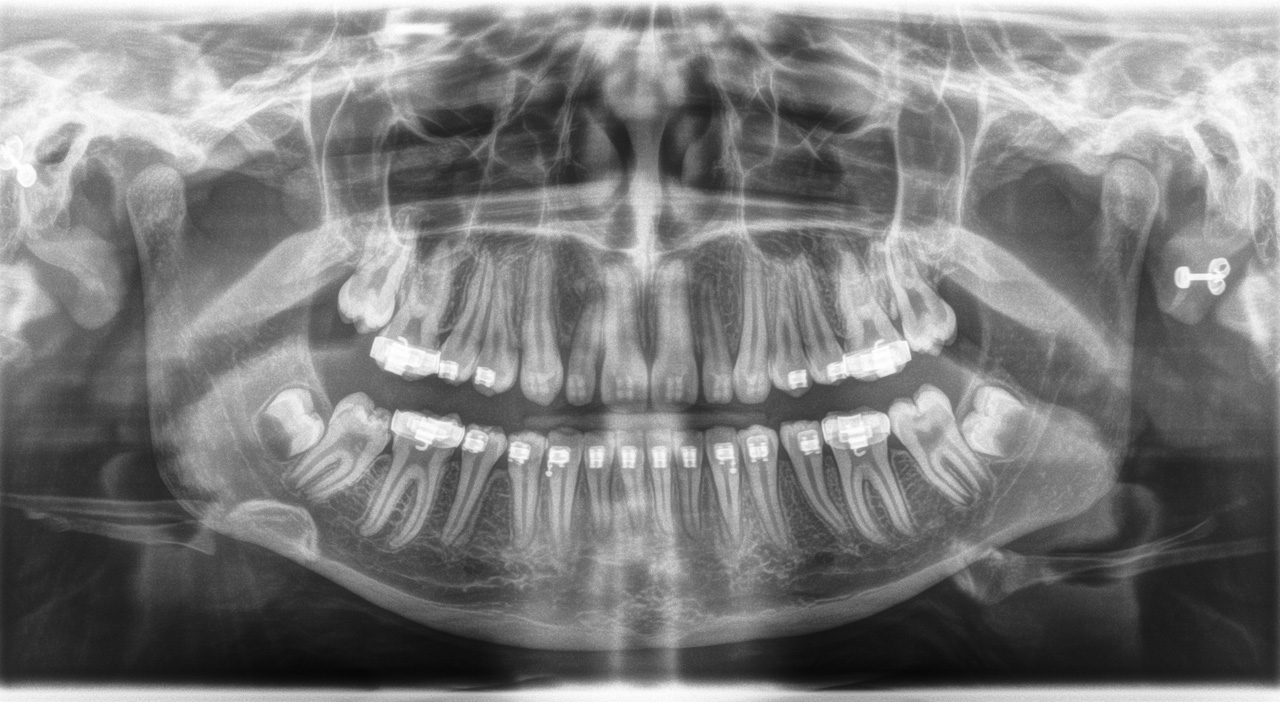

Adolescent, full dentition with orthodontic braces